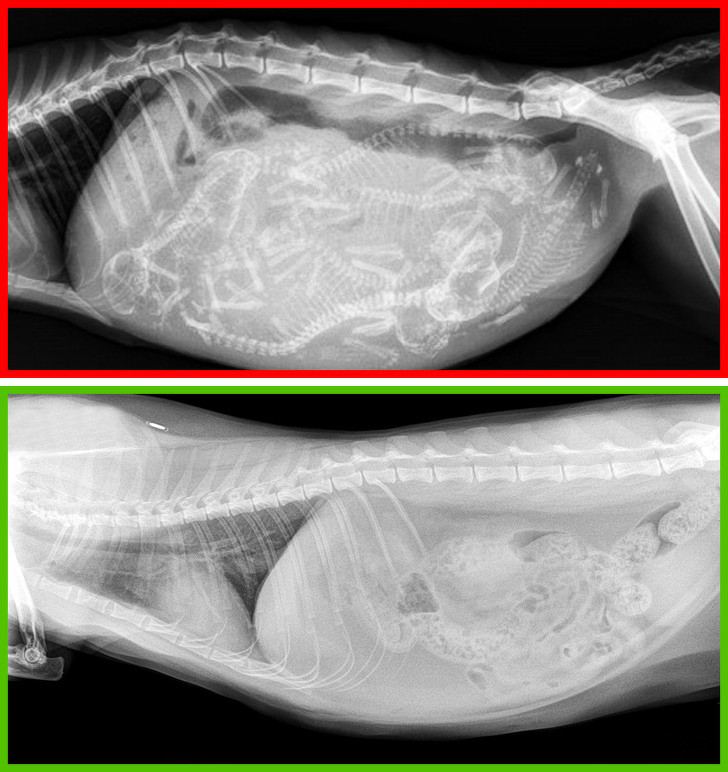

1. Cắt móng chân quá ngắn

Cắt móng chân cho mèo là hành động phản khoa học, thậm chí bị cấm ở nhiều quốc gia. Khi cắt không đúng cách, mèo cưng có thể phải chịu những cơn đau dữ dội ở bàn chân khi di chuyển.